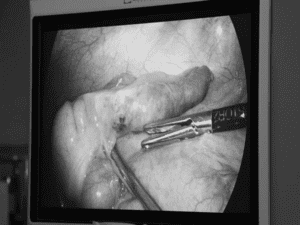

Mổ ruột thừa bất ngờ phát hiện xương cá đâm xuyên thành ruột hiếm gặp

Suckhoedoisong.vn – Trong quá trình mổ cấp cứu cắt viêm ruột thừa cho bệnh nhân, [...]